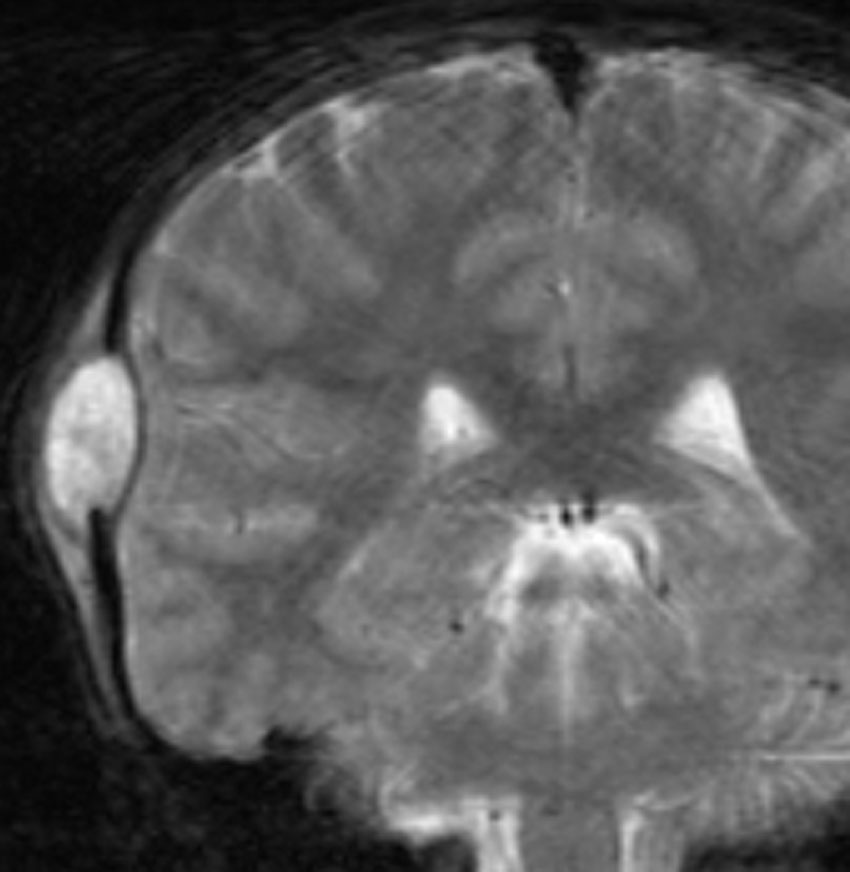

脳のLCH(ガドリニウム増強されるタイプ)

- 左の写真は,両側の側頭葉内側(黄色の矢印)と視床下部(赤)に同時にできたLCHです

- このように脳のLCHは近寄った場所に多発するように散在性に発生することがあります

- まれには,前頭葉全域にガドリニウム増強病変が生じて,悪性グリオーマと間違うようなものもあります

- これを単発病変とするのか1臓器の多発病変とするのかはわかりません

- 左の写真は3ヶ月後のものですが,なにも治療しないで自然に病巣は消失してしまいました(自然寛解)

- しかし,脳のLCHは脳組織を破壊して広がりますから,病像が消えても症状は後遺症として残ることが多いです

- ですから,脳病変が発見されたら正確に診断して治療を行った方がいいでしょう